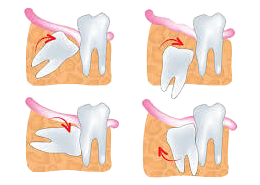

親知らずとは、一番奥にある歯(第3大臼歯)のことです。20才前後で生えそろえてくる永久歯です。親知らずが問題なのは生え方です。真っ直ぐ、しっかり生えている親知らずはもちろんそのままで大丈夫です。しかし、斜めに生えている、噛み合わせ等で歯として機能していない場合は、手入れが難しく虫歯になってしまうことが多いです。また、骨や歯ぐきの中に収まっているものもあります。(埋伏歯)

親知らずとは、一番奥にある歯(第3大臼歯)のことです。20才前後で生えそろえてくる永久歯です。親知らずが問題なのは生え方です。真っ直ぐ、しっかり生えている親知らずはもちろんそのままで大丈夫です。しかし、斜めに生えている、噛み合わせ等で歯として機能していない場合は、手入れが難しく虫歯になってしまうことが多いです。また、骨や歯ぐきの中に収まっているものもあります。(埋伏歯)

生え方によって痛みや隣の歯に悪影響を与えることもあります。そういった場合、抜歯をおすすめします。